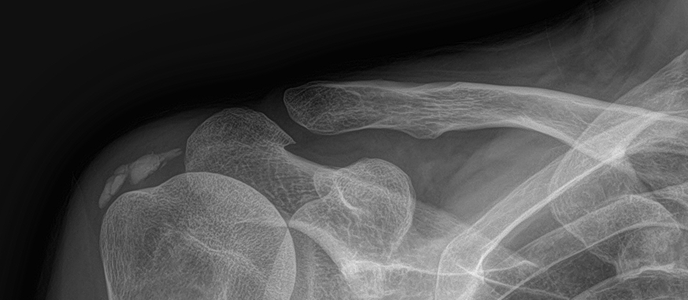

석회쇄석술 전후사진

치료 증상 갑자기 팔 들기 힘듦, 밤에 아픔

나이/성별 55세 / 남성

치료 내용 석회쇄석흡인술 후 호전

치료 기간 2024-11-22 ~ 2025-02-22